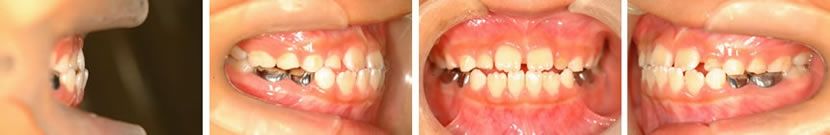

11歳女子(治療コース:Ⅰ期治療の一部/非抜歯症例/装置をつけていた期間1年6か月)

上顎両側側切歯先天欠如症例

| 症例 |

|

||

|---|---|---|---|

| 院長コメント & 治療のリスク |

生まれつき上の前歯が2本無いために、すきまが大きく残っていましたが、早期の治療によってすきまをきれいに閉じることができました。 |